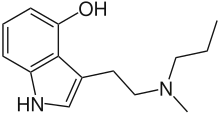

Substituted tryptamines, or serotonin analogues, are organic compounds which may be thought of as being derived from tryptamine itself. The molecular structures of all tryptamines contain an indole ring, joined to an amino (NH2) group via an ethyl (−CH2–CH2−) sidechain. In substituted tryptamines, the indole ring, sidechain, and/or amino group are modified by substituting another group for one of the hydrogen (H) atoms.

| Chemical structure | Short Name | Origin | Ring Substitution | RN1 | RN2 | Full Name | CAS Number |

|---|---|---|---|---|---|---|---|

| Tryptamine | Animals, plants, fungi | H | H | H | 3-(2-aminoethyl)indole / 2-(1H-indol-3-yl)ethanamine | 61-54-1 |

| NMT | Plants | H | H | CH3 | N-methyltryptamine | 61-49-4 |

| 2-HO-NMT | Plants | 2-OH | H | CH3 | 2-hydroxy-N-methyltryptamine | 106987-89-7 |

| 5-MeO-NMT | Plants | 5-OCH3 | H | CH3 | 5-methoxy-N-methyltryptamine | 2009-03-2 |

| Serotonin | Animals, plants | 5-OH | H | H | 5-hydroxytryptamine | 50-67-9 |

| Nω-Methylserotonin (norbufotenin) | Plants | 5-OH | H | CH3 | 5-hydroxy-N-methyltryptamine | 1134-01-6 |

| Bufotenin | Animals, plants, fungi | 5-OH | CH3 | CH3 | 5-hydroxy-N,N-dimethyltryptamine | 487-93-4 |